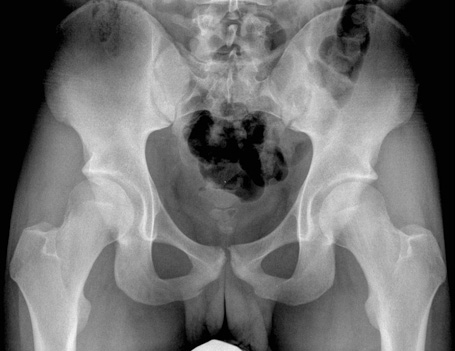

Female Pelvis

Anterior Inferior Iliac Spine

Anterior Superior Iliac Spine

Femoral Head

Femoral Neck

Femur

Greater Trochanter

Iliac Crest

Inferior Pubic Ramus

Ischial Ramus

Ischial Spine

Lesser Trochanter

Obturator Foramen

Pubic Symphysis

Sacrum

Superior Pubic Ramus